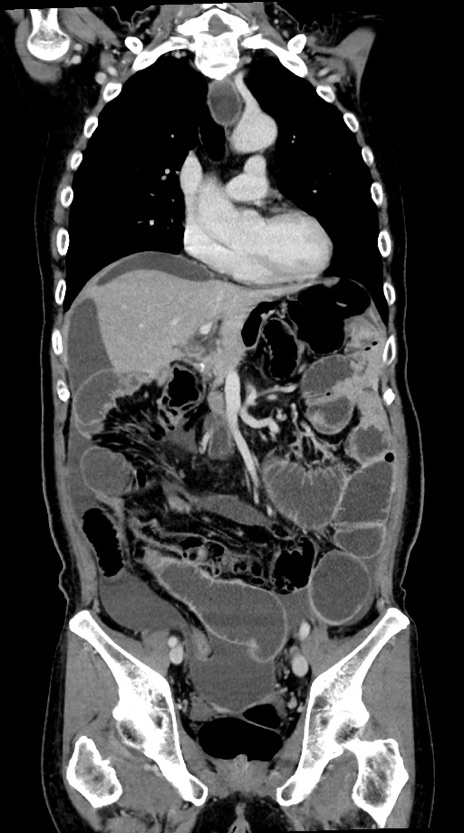

横断像

【症例】60歳代男性

【主訴】嘔吐

【現病歴】胃癌にて胃全摘後。食思不振が悪化し、夜中に嘔吐することがある。

【既往歴】胃癌、胃全摘、脾摘、胆摘後

【データ】WBC 5900、CRP 10.56